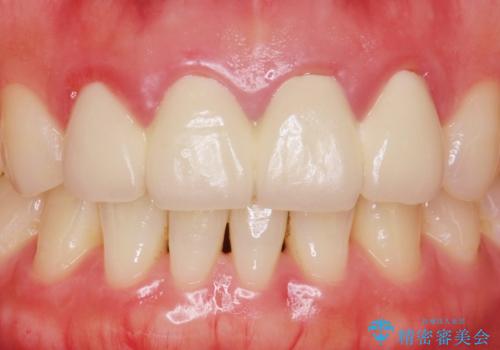

自然な仕上がりに大変喜んで頂けました。

単冠かつ適合の良いクラウンにより清掃性が良くなり、歯茎の腫れ・出血もなくなりました。

天然歯と見紛うほど自然なセラミッククラウンは、熟練した技工士さんの技術の賜物です。

クラウンの種類:ジルコニアオールセラミッククラウン エクセレント